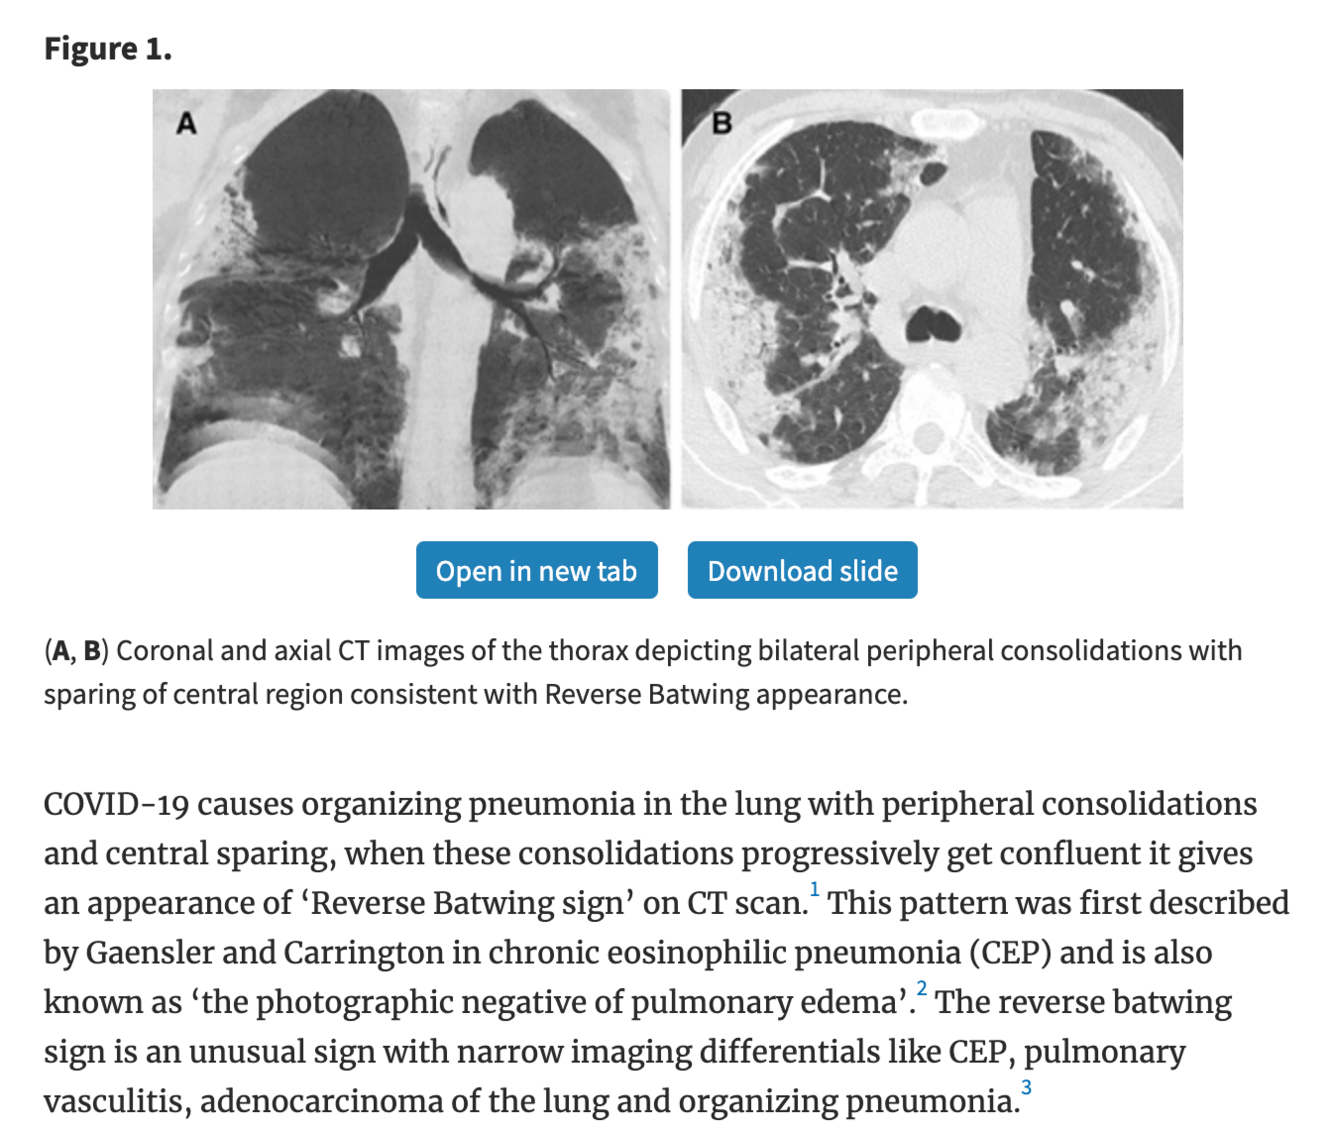

“reverse bat wing”

This refers to peripheral opacities of the lungs, sparing the perihilar region. It is a relatively unusual appearance with a relatively narrow differential